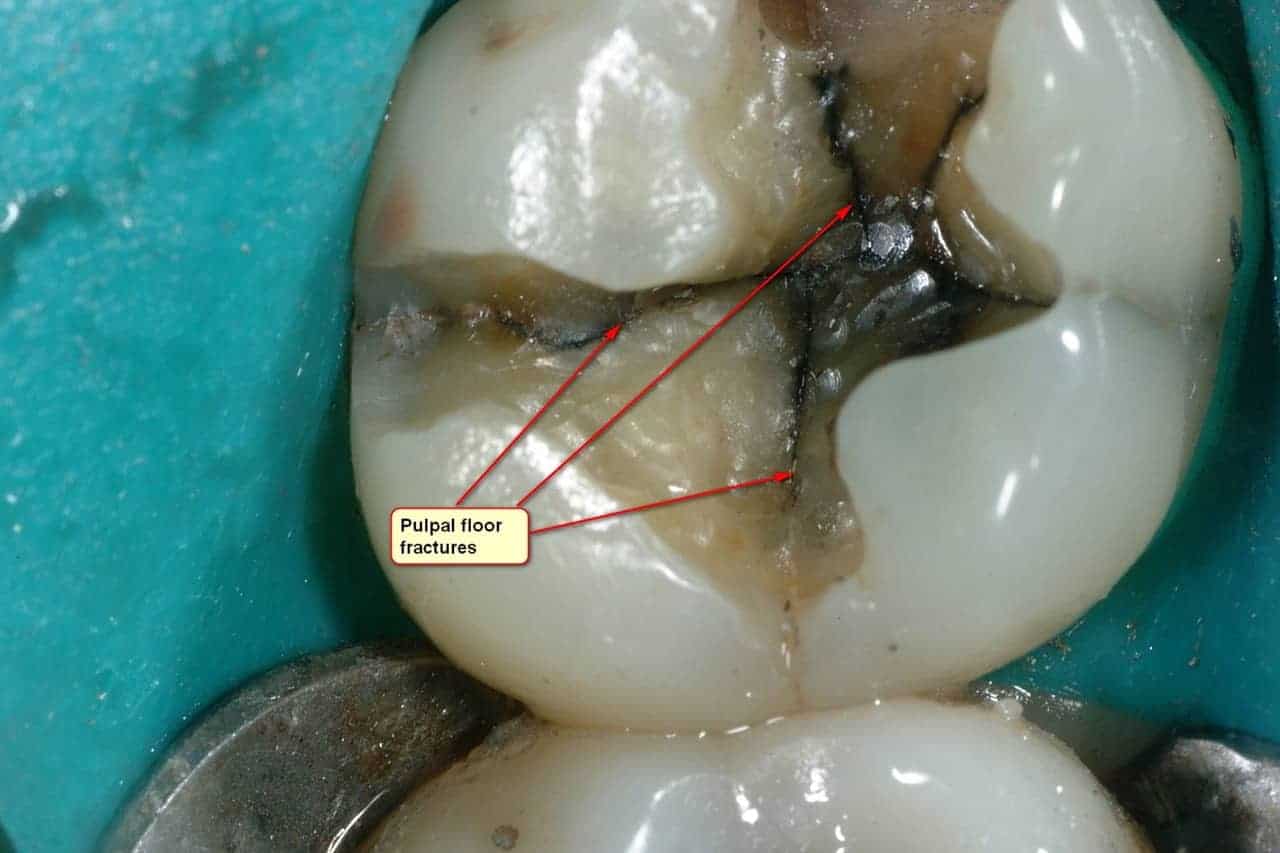

Do Amalgam Fillings Cause Teeth To Crack . Dental amalgam fillings are sometimes called silver fillings. Science has proved that the mercury in fillings do not cause these diseases; Cnn — the us food and drug administration warned thursday that silver dental fillings, known as dental amalgam, may cause health problems for some. Drilling out large cavities to accommodate mercury amalgam filling(s) can destroy parts of the tooth that actually help to hold the tooth together. They are the most common type of filling used in canada. Cracked tooth syndrome occurs when a large silver amalgam filling acts as a wedge cracking the tooth structure around the filling. A, occlusal view of tooth #3 with vertical fractures extending from a defective amalgam restoration over the mesial marginal ridge and down the mid.

They are the most common type of filling used in canada. A, occlusal view of tooth #3 with vertical fractures extending from a defective amalgam restoration over the mesial marginal ridge and down the mid. Drilling out large cavities to accommodate mercury amalgam filling(s) can destroy parts of the tooth that actually help to hold the tooth together. Cracked tooth syndrome occurs when a large silver amalgam filling acts as a wedge cracking the tooth structure around the filling. Science has proved that the mercury in fillings do not cause these diseases; Dental amalgam fillings are sometimes called silver fillings. Cnn — the us food and drug administration warned thursday that silver dental fillings, known as dental amalgam, may cause health problems for some.